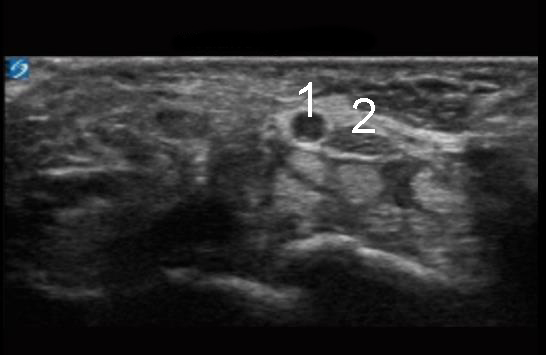

Wrist Carpal Tunnel Median Nerve Image

Median Artery

Median Nerve